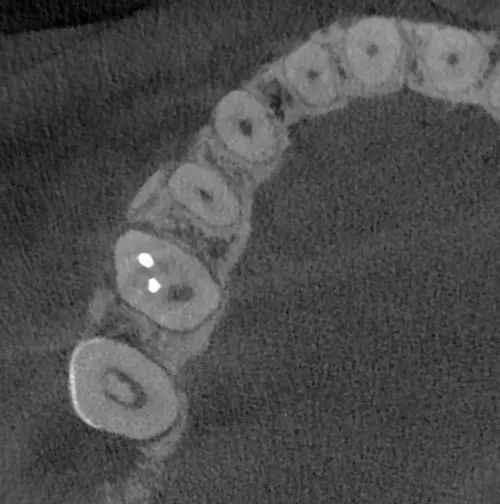

TOMOGRAFÍA PARA ENDODONCIA

Evaluación necesaria en campo reducido para visualizar los conductos radiculares o probables fracturas.